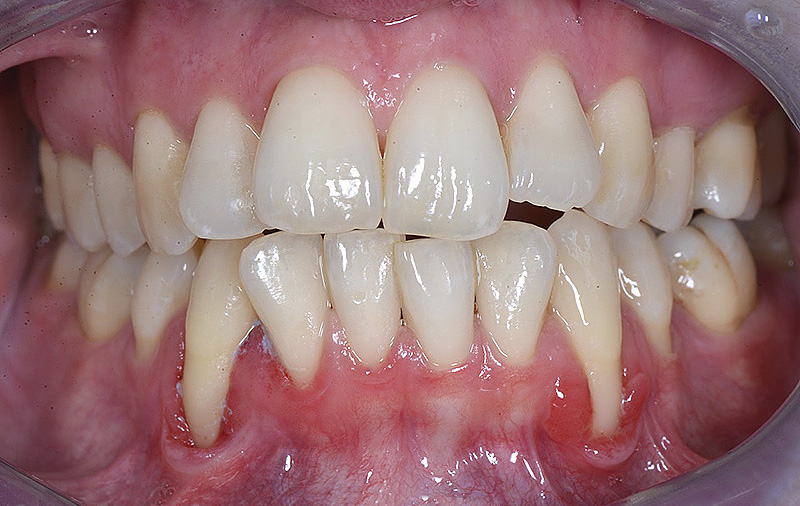

PREMESSA: in seguito all’estrazione dell’incisivo laterale superiore di destra, resasi necessaria per cause batteriche, si decide di affrontare il caso con il posizionamento di un impianto in sostituzione dell’elemento mancante dopo guarigione del sito infetto. Con tecniche rigenerative sia dei tessuti ossei mancanti a causa dell’infezione pregressa, sia dei tessuti gengivali che appaiono inizialmente troppo spostati in alto, si ripristina una corretta morfologia delle parabole (contorni) gengivali e delle papille interdentali (triangoli di gengiva tra due denti vicini).

Vengono utilizzati 2 tipi di provvisori: il primo, cementato ai denti vicini, viene utilizzato dal momento dell’estrazione del dente fino ad impianto osteointegrato (circa 6 mesi); il secondo, avvitato direttamente all’impianto, ha una funzione di prova estetica ma soprattutto di guida per la maturazione dei tessuti gengivali peri-implantari portandoli verso la maturazione completa prima di posizionare la corona finale in disilicato di litio.